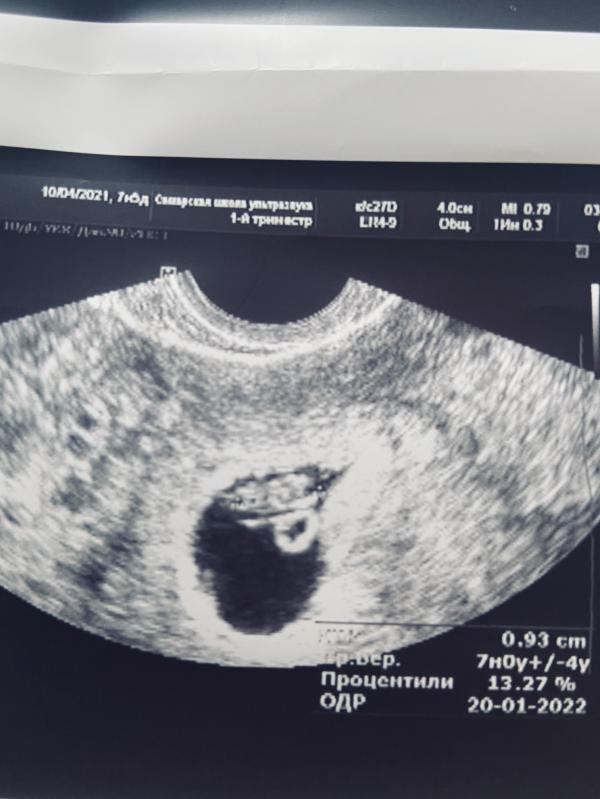

7 недель и 6 дней -Акушерский срок.

По узи 7недель.

К.т.р. - 9,3 мм. (Размер эмбриона)

Но вроде как самый опасный период этой гематомы прошёл (она должна рассосаться или выйти .площадь гематомы 0,56 кВ.см. Не маленькая...

Сердечко стучит 133 удара.